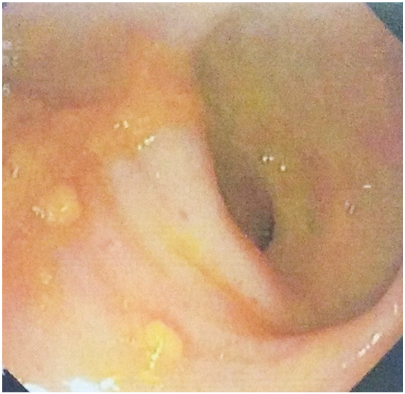

A 24years male presented with history of passing stool three to four times per day. He felt constipated. He was having a sensation to pass stools many times a day. Every time he went to pass stools he was passing small amount of well formed stools with straining at stools. He was passing small quantity of mucous along with stools. Oral metronidazole 400mg thrice daily along with syrup lactulose was prescribed for seven days with clinical diagnosis of amoebic proctocolitis. There was no relief in symptoms. After another ten days the patient was passing stools along mucous and blood three to four times per day. The colonoscopy was done in this patient with report as two ulcers on the anterior rectal wall. The ulcers were circular about 2cm diameter having greyish white floor with raised margin. There was hyperaemia all around (Figure 1). On endoscopic appearance the diagnosis of solitary rectal ulcer syndrome (SRUS) was suggested. The biopsy from the margin of ulcer revealed chronic inflammatory cells and fibroblast in the lamina propria. The patient was treated by conservative treatment which consisted of bulk laxative.

Figure 1 Endoscopic view of Solitary Rectal Ulcer Syndrome.